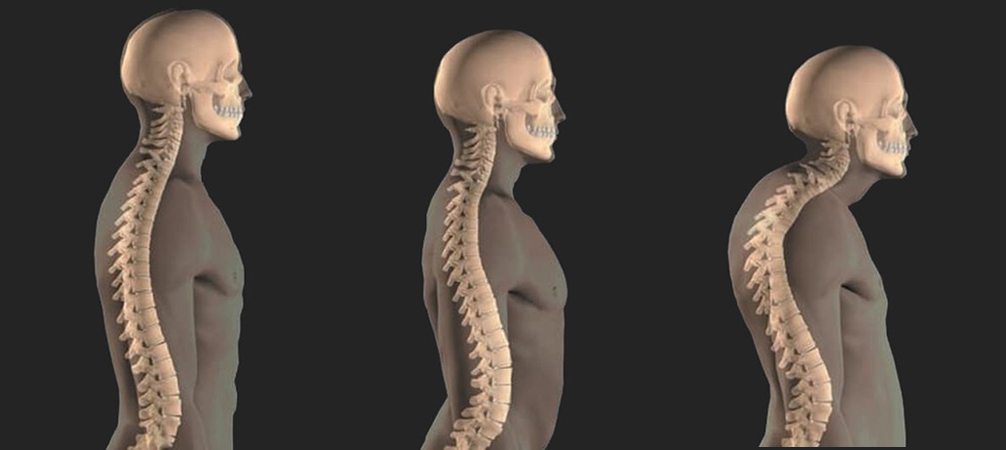

"Холка", или вдовий горб — это жировое отложение в области седьмого шейного позвонка, которое может сопровождаться нарушением осанки и деформацией верхнего отдела позвоночника. Медицински это состояние в Фокино известно как кифоз шейно-грудного отдела или дорсоцервикальный жировой бугорок. Чаще всего проблема возникает у женщин в период менопаузы, когда гормональные изменения влияют на перераспределение жира в организме. Несмотря на то, что на первых этапах это воспринимается как эстетический недостаток, "холка" может стать причиной серьезных проблем с опорно-двигательной системой, включая хронические боли, ограничение подвижности шеи и нарушение кровообращения.

Вдовий горб, или дорсоцервикальный жировой бугорок, представляет собой локальное скопление жировой ткани в области перехода шейного отдела позвоночника в грудной. Эта зона, известная как седьмой шейный позвонок, становится уязвимой к образованию отложений жира и изменению структуры мягких тканей по мере старения организма, особенно у женщин. Основные факторы, способствующие развитию вдовьего горба, включают гормональные изменения, такие как снижение уровня эстрогена в период менопаузы, что ведет к нарушению перераспределения жира.

Хотя сутулость и вдовий горб внешне могут выглядеть схожими, между ними существует принципиальное различие. Сутулость — это нарушение осанки, связанное с перераспределением мышечного тонуса и увеличением грудного кифоза, тогда как вдовий горб — это патологическое жировое отложение, которое возникает вследствие метаболических и гормональных изменений. Важно отметить, что сутулость может способствовать развитию горба, так как нарушенная осанка увеличивает давление на шейно-грудной переход, усугубляя деформацию.

Если оставить проблему без внимания, жировое отложение будет увеличиваться в размере, что может привести к более выраженной деформации позвоночника. Это может вызвать хронические боли в области шеи и верхней части спины, ограничить подвижность, а также повлиять на кровообращение и иннервацию в этой области. Со временем симптоматика усиливается, и проблема требует комплексного подхода для исправления, включающего коррекцию осанки, физические упражнения и медицинское вмешательство.

2. Нарушение осанки и ухудшение подвижности